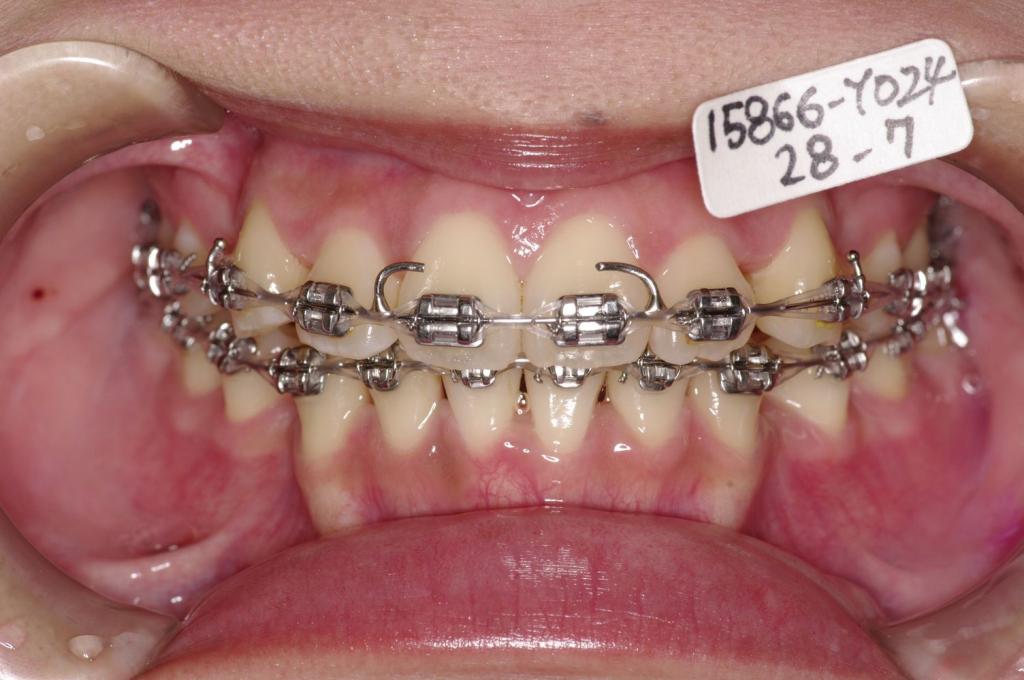

- 前歯、出っ歯・開咬の矯正治療

- 前歯が出ている

- 上下の前歯の間に舌を入れる癖がある場合には、歯の裏側にフックを付ける場合があります。その場合発音がしにくくなったり、食事の時に舌が痛かったりすることがあります。